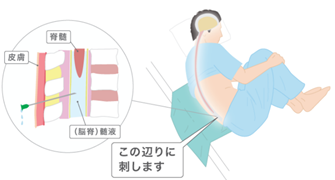

水頭症のひと 脳神経外科の病気:水頭症 | 病気の治療 | 徳洲会グループの詳細情報

脳神経外科の病気:水頭症 | 病気の治療 | 徳洲会グループ。特発性正常圧水頭症(とくはつせいせいじょうあつすいとうしょう。診断と検査|高齢者の水頭症 iNPH.jp。iNPHとは?|高齢者の水頭症 iNPH.jp。絵画の種類...油彩画・油絵形式...掛け軸・掛軸主題...人物・肖像壁掛けアート贄田越郎画主な画材...油彩絵の具